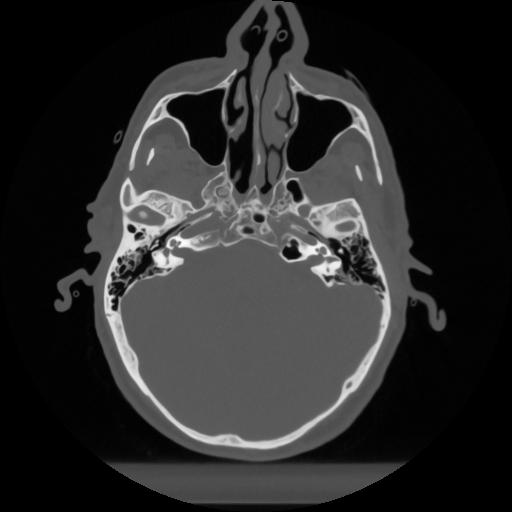

12 P.BLANDAS,,Vol,0.5,P.BLANDAS,,